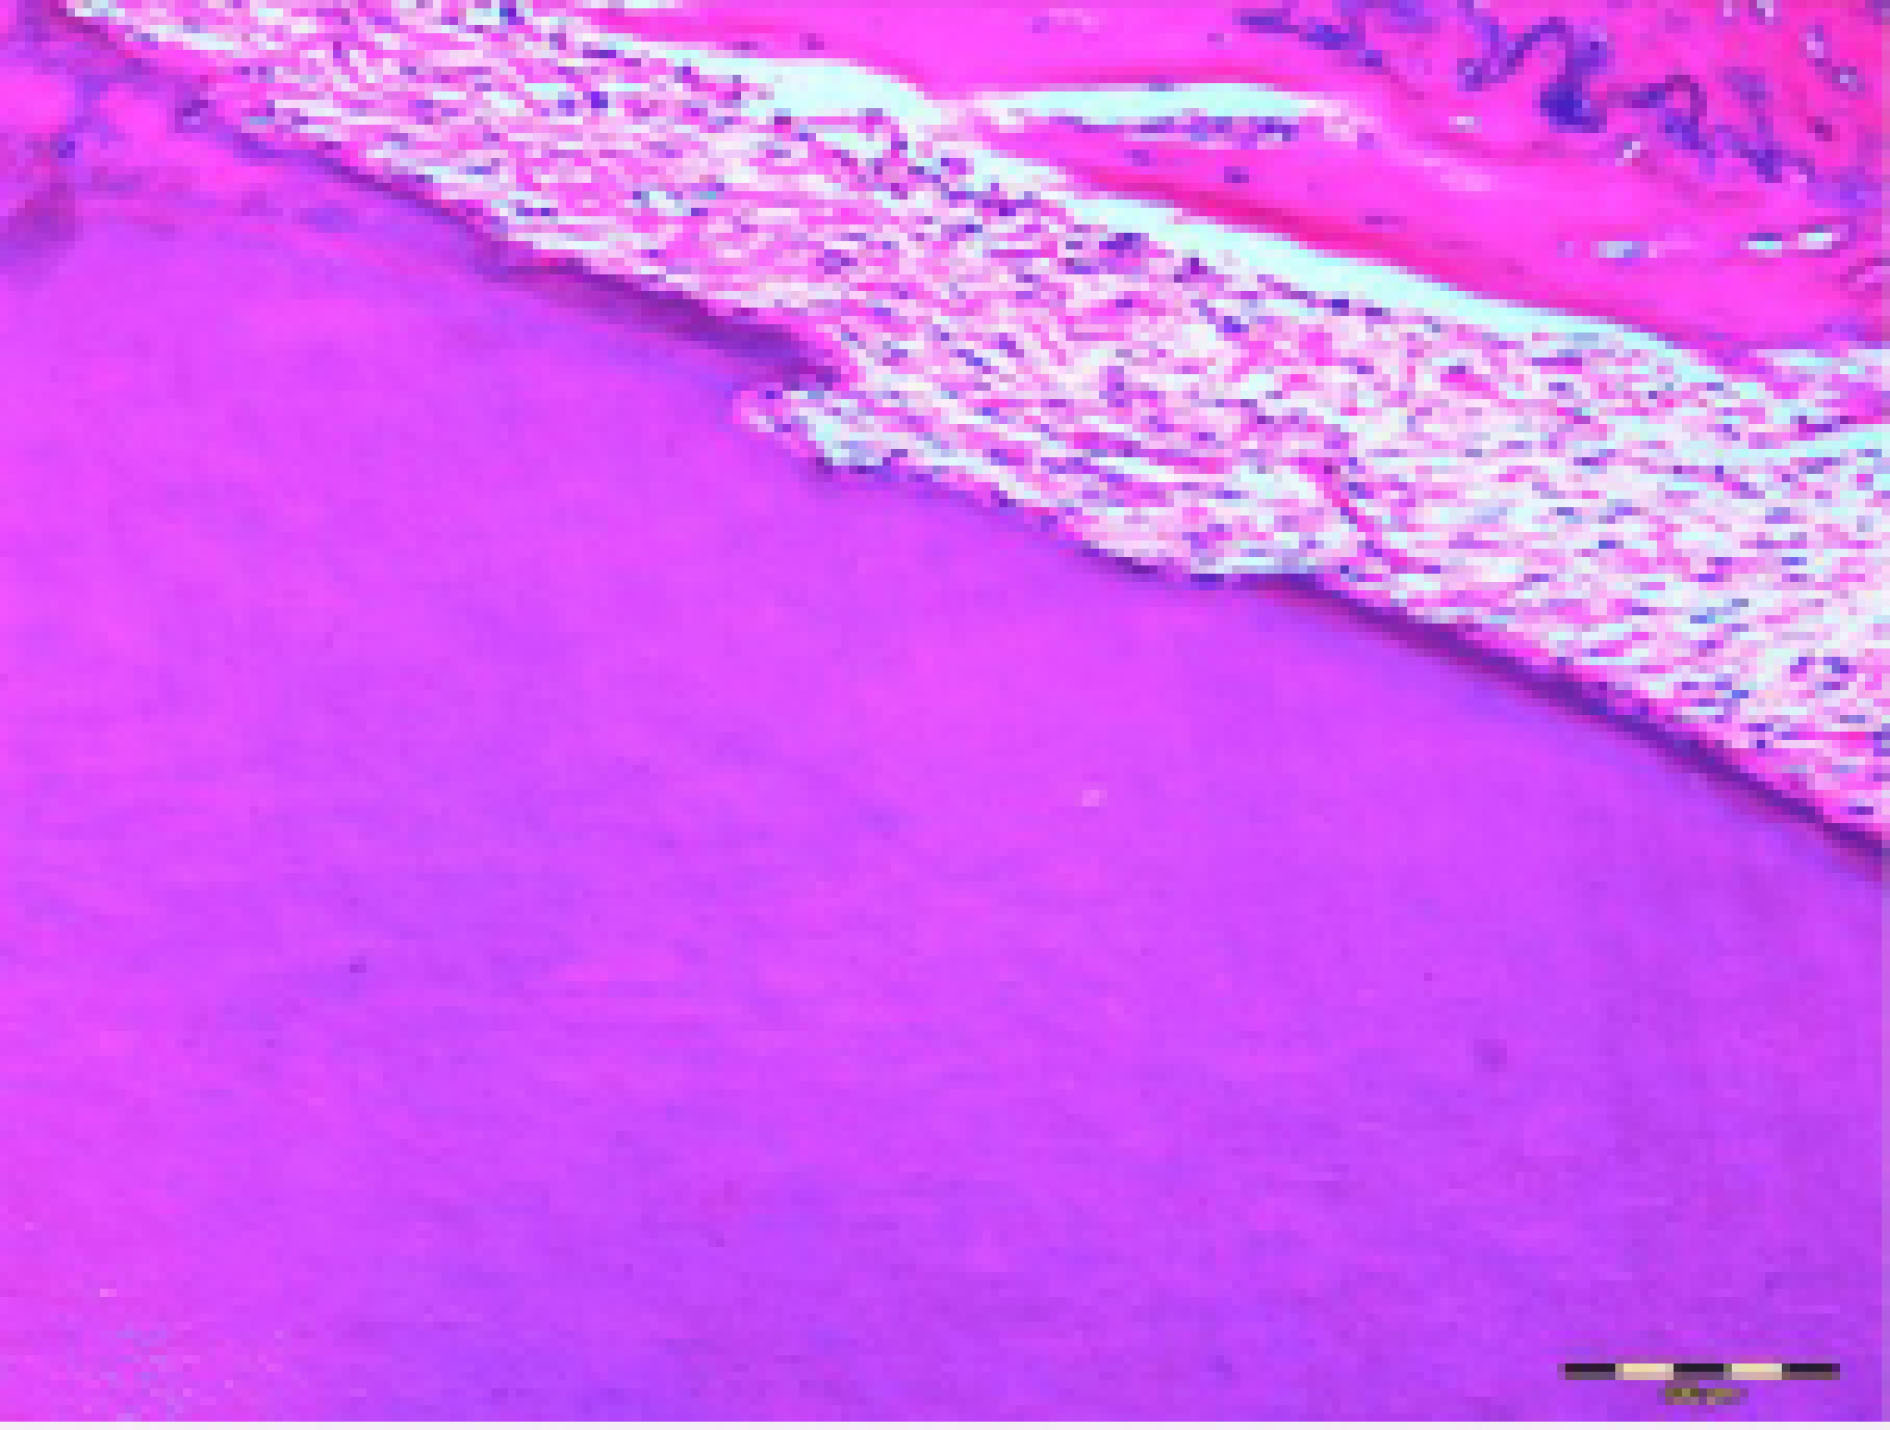

The width and depth of the resorptive lacunae () were assessed on both the mesial and distal surfaces of the mesial root of the first molars, in addition to counting the osteoclasts, to determine root resorption.

16

As demonstrated in , osteoclasts were identified as multi-nucleated cells with abundant, slightly basophilic to bright, eosinophilic cytoplasm.

Figure 2.

Microscopic section of the mesial root of the first molar and alveolar bone containing resorptive lacuna (magnification ×400).